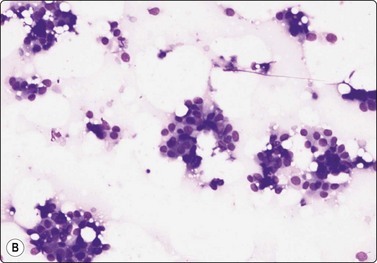

Breast tissue in pregnancy and lactation (Fig. 7.8)

image image image

Fig. 7.8 Lactating breast

Dispersed acinar cells with abundant pale and fragile cytoplasm, rounded nuclei and prominent central nucleoli; background of lipid secretions (A, MGG, HP; B, H & E, HP oil); (C) Corresponding tissue section (H&E, IP).

Criteria for diagnosis

Cellular smears,

Poorly cohesive, mainly dispersed epithelial cells of acinar type,

Cells have abundant fragile cytoplasm with secretory vacuoles and frayed borders,

Rounded vesicular nuclei and central nucleoli,

Dirty background due to lipid secretion and stripped nuclei with prominent nucleoli,

Single bipolar nuclei difficult to find.

FNB is very useful in reducing surgical intervention to a minimum during pregnancy and lactation. The pattern seen in FNB smears of ‘lumps’ in a pregnant or lactating breast can be problematic to inexperienced eyes and cause concern for malignancy.93,94 Smears are usually cellular. The cells are enlarged and arranged in loose groups or singly. The cells have an abundant fragile cytoplasm, vacuolated and finely granular. Nuclei are round, central, larger than the usual ductular cells, and have distinct small nucleoli (Fig. 7.8B). Some epithelial nuclei are stripped of cytoplasm. Single naked bipolar/oval nuclei are difficult to find. The background of abundant milky secretion with numerous lipid droplets seen as vacuoles is characteristic of actively secreting breast tissue and is the main clue to the diagnosis (Fig. 7.8A).